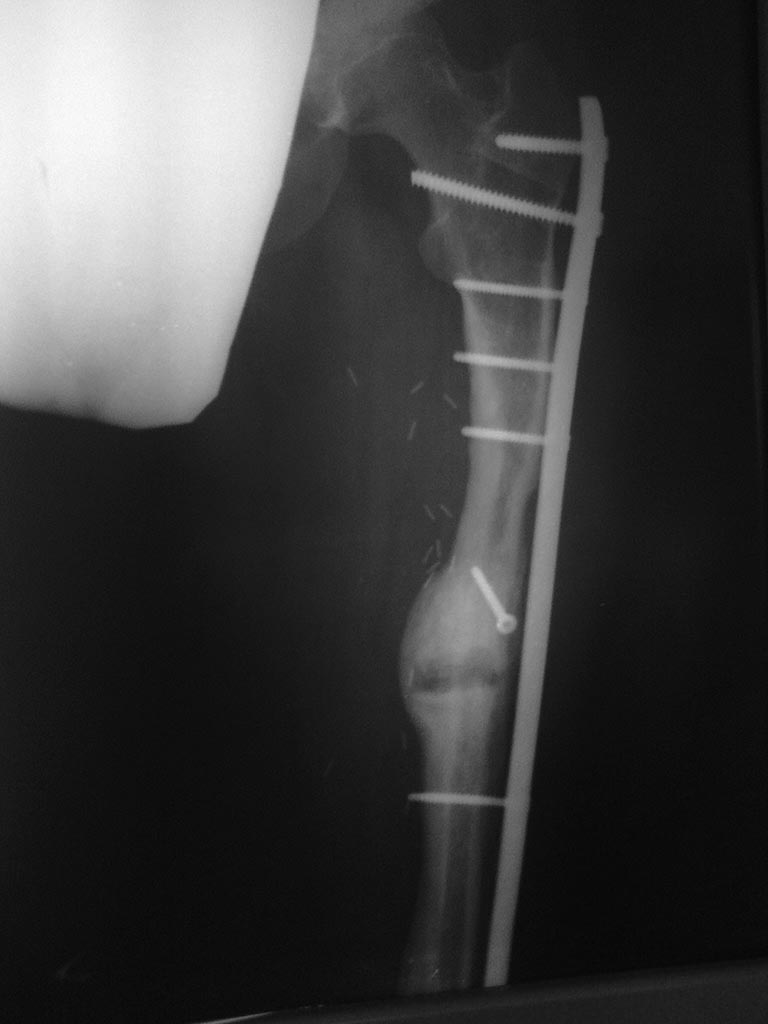

Уважаемые коллеги, нужен совет. Девочка, 18 лет, остеогенная саркома 2010 год, резекция, замещение свободным васкуляризированным трансплантатом малоберцевой кости с остеосинтезом L-образной пластиной. Пластина удалена в 2011 году после консолидации концов трансплантата и проксимальных и дистальных концов бедренной кости (хотя нестабильность конструкции, миграция винтов имело место быть. В 2012 году несколько переломов трансплантата, лечение консервативное. Сентябрь 2012 после очередного перелома открытая репозиция, костная аутопластика кортикально-губчатым трансплантатом из крыла подвздошнй кости с МОС пластиной с угловой стабильностью. Интраоперационно - без особенностей. В период динамического наблюдения на фоне образования костной мозоли отмечается литическая деструкция концов костных отломков в зоне перелома (снимки - 1 мес, 2.5 мес и 3.5 мес после операции. Что это? Метастаз? Откуда (из крыла?) Нестабильность(признаков нет..)? Какую тактику посоветуете? Спасибо.

пластина по индивидуальному заказу, все винты с угловой стабильностью, дистально, по моему, винтов 7 - 8 (аналог дистальной мыщелковой пластины). Толщина винтов в средней части определялась толщиной трансплантата малоберцевой кости. Отдельный кортикальный винт в с/3 - фиксация аутотрансплантата крыла бок в бок. в плане нестабильности - деформации винтов, их миграции, резорбции костной ткани вокруг них нет. Смущает кистообразная литическая полость в зоне перелома с тенденцией к увеличению . Пока дали антирезорбенты...

На последнем снимке лизис не только в зоне перелома, но выше (меньше) и ниже (больше) со стороны пластины. И не похоже, что это связано с нестабильностью. И почему метастаз. Радикально резецировать остеогенную саркому не всегда удается. Скорее не часто. По-моему нужна биопсия, а потом уже решать, что делать.